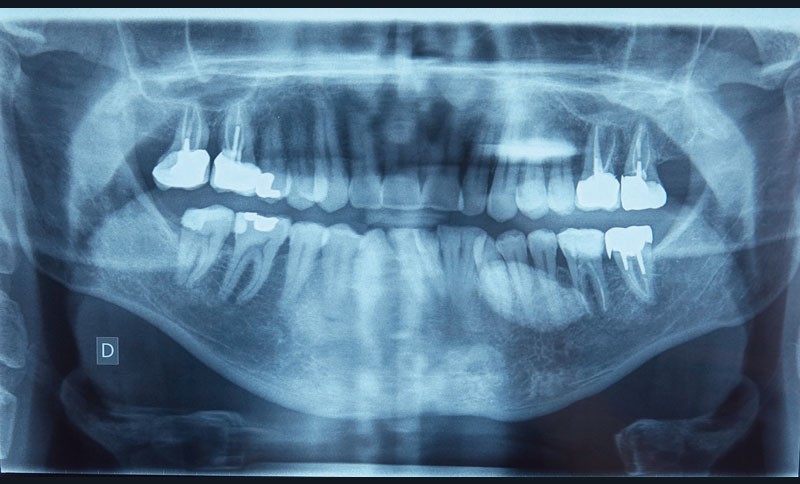

Une radiographie panoramique, une échographie de la loge submandibulaire gauche et un cliché occlusal permettent de compléter l’examen clinique.

Sur la première (fig. 2), on retrouve au niveau du secteur 3 une lésion radio-opaque de plusieurs centimètres, homogène, de forme arrondie aux contours bien délimités, et sans rapport avec les apex des dents présentes.